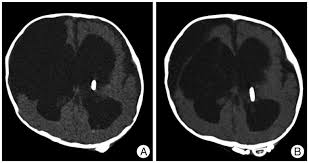

Brain Ct Scan Before Extraction Of Ventriculoperitoneal Shunt Download Scientific Diagram

Brain Ct Scans Showing Normal Ventricles After Ventriculoperitoneal Download Scientific Diagram